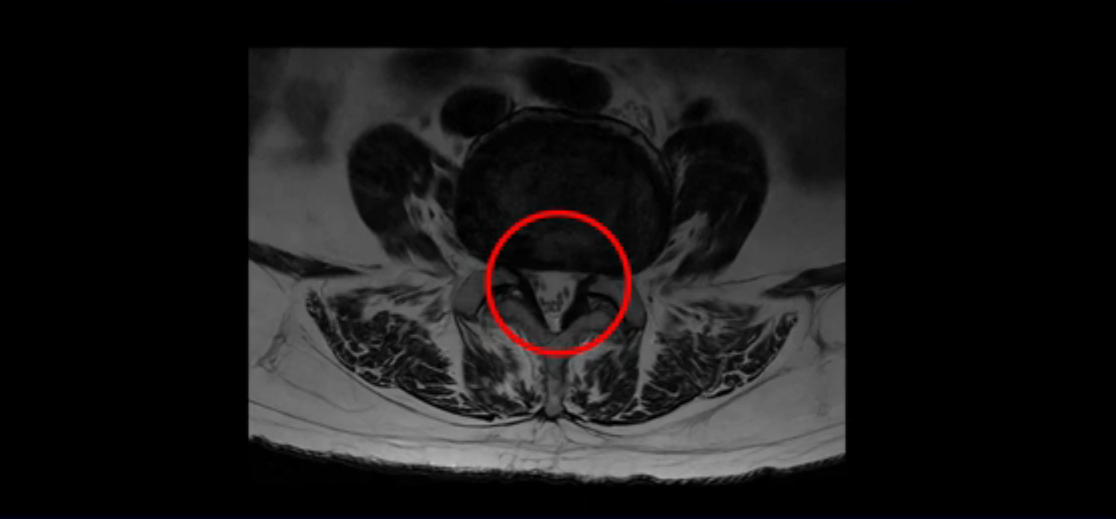

보시다시피 이 환자분은 허리 여러 마디가 다 안 좋습니다. 4마디 디스크 높이가 심하게 주저 앉았습니다.

척추관도 좁아져 있습니다.

이렇게 신경 구멍들이 좁아져 있어서 신경눌림 증상이 엉덩이와 다리에 생기는데, 이런 증상들은 근육과 매우 밀접한 관련이 있습니다.

협착증 환자분들 중 걸을 때만 다리가 저리고 아픈 분들이 있고, 반면에 앉거나 누울 때도 허리, 엉덩이, 다리가 아프고 저린 분들이 있습니다. 이 환자분처럼 앉아도 누워도 아픈 분들일수록 근육 문제가 심한 분들이고, 이런 분들은 걸을 때만 아픈 분들에 비해 수술 결과도 더 안 좋고 따라서 수술 이후에도 아플 가능성이 높습니다. 꼭 알아두시길 바랍니다. 저희 모커리한방병원에서는 걸을 때만 다리가 저리고 아픈 분들을 단순형 협착증, 걸을 때 말고도 앉거나 누울 때도 허리, 엉덩이와 다리가 저리고 아픈 분들을 복합형 협착증이라고 부르는데, 이 환자분이 바로 복합형 협착증 환자분입니다.